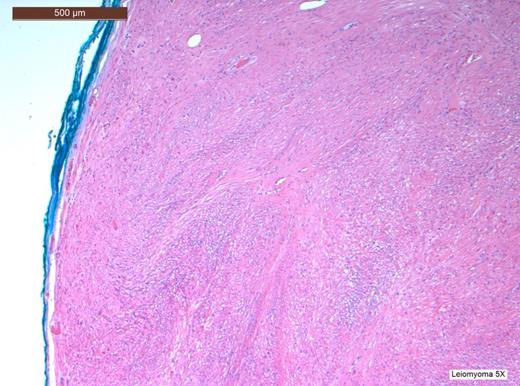

Histopathological analysis of the lesion, including immunohistochemical profiling, revealed a well-circumscribed nodular tumour composed of smooth muscle cells with eosinophilic cytoplasm and spindle-shaped nuclei. The cells were arranged in interlacing fascicles with evidence of perinuclear vacuoles using haematoxylin and eosin staining. There was no evidence of necrosis, mitosis or significant nuclear pleomorphism. The specimen was negative for CD117 staining, hence excluding the possibility of a gastrointestinal stromal tumour. It was also negative for S100. However, stain was positive for smooth muscle actin (SMA) and desmin, which confirmed that specimen was of muscular origin. The histology therefore identified the lesion as a leiomyoma (Figs 2–6).

H&E stain at high power view showing spindle-shaped cells and perinuclear vacuoles, a characteristic finding of leiomyomas.